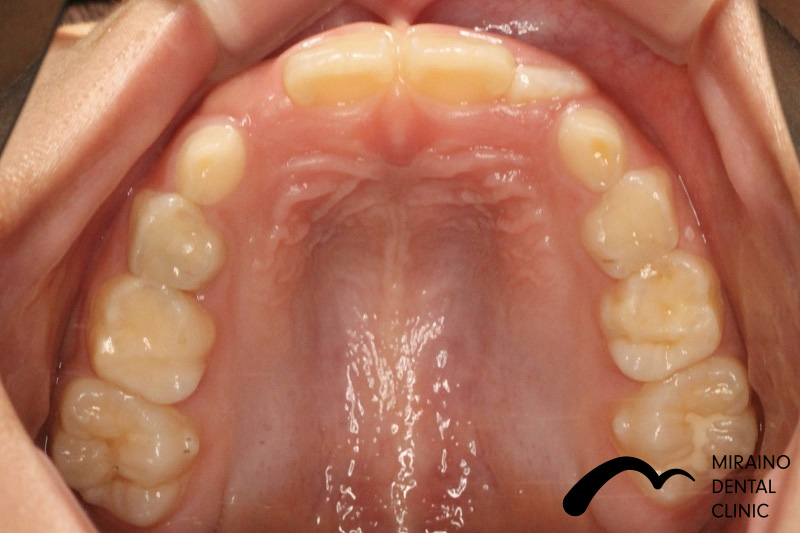

叢生(ガチャガチャ・ガチャ歯)①

| 施術名 | マウスピース矯正(インビザライン) |

| 施術の内容 | 歯科矯正でも目立ちにくい新しい矯正方法です。 透明に近いマウスピース型の矯正装置(アライナー)のため、歯に装着しても目立つことなく歯並びを矯正することが出来ます。 また、一人ひとりの合わせて矯正装置を作製いたします |

| 治療費 | インビザライン990,000円 |

| 考えられるリスク、副作用 | 疼痛・咬合時痛を生じる事があります。 時間経過とともに治ります。 |

| 考えられるリスク、副作用[矯正] | 継続使用により緩んだり、外れやすくなる事があります。 割れたり壊れたりする事があります。 諸々の事情により、治療期間が当初よりも伸びる事があります。 所定の装着時間22時間を守って頂けない場合、治療計画どおりに治らない可能性があります。 歯が動く際に、痛みが出る事があります。 矯正期間中は虫歯や歯周病のリスクが高まりますので、しっかりとしたケアが必要です。 歯の移動に伴う歯肉退縮や歯根吸収が起こる事があります。 インビザライン・システム(invisalignR)は、アメリカのアラインテクノロジー社より提供されている、カスタムメイドの矯正装置ならびに、これを用いた治療システムを指します。 インビザラインを用いた治療は保険適用外の自由診療となります。 厚労省の認可(医薬品医療機器等法上の承認)は得ていないため、まだ明らかになっていないリスクが存在する可能性があることをご了承ください。 |

| 全て | 必ずしもご希望通りの見た目にならない事があります。 |